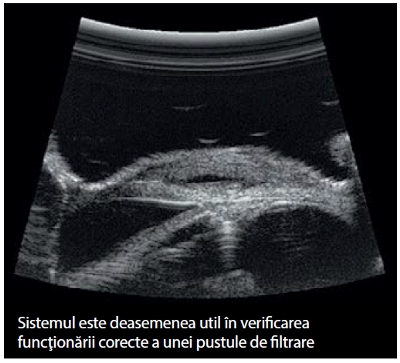

Sistemul ultrasonografic oftalmologic este util deasemenea pentru a verifica funcţia pustulei la pacienţii cu filtraţii. Sistemul cu unghi larg vă poate ajuta în urmărirea clară a căii apoase, cât şi la vizualizarea filtrării, ajutând astfel la îmbunătăţirea diagnosticuluii funcţionalităţii pustulei.